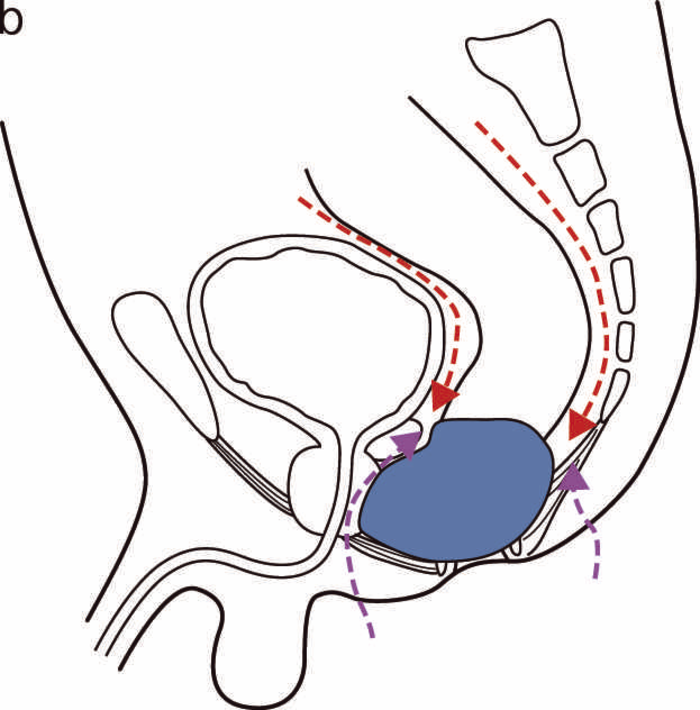

2. CD関連直腸肛門管腫瘍

本邦のCD関連消化管腫瘍では直腸肛門管癌(痔瘻癌を含む)が最も多い。過去の報告では直腸肛門管癌に対しては,低位前方切除術,腹会陰式直腸切断術が行われているが,最も多いのは腹会陰式直腸切断術である2)CQ 18)。本邦と同様に腺癌が多い韓国からの報告でも腹会陰式直腸切断術が多い3)。欧米の痔瘻に関連した癌の報告では放射線化学療法が施行されている症例もあるものの,扁平上皮癌の症例があることが影響している4)

通常の大腸癌に準じ,腫瘍の局在や深達度,リンパ節転移などを加味し,さらにCDの病変範囲と状態を診て術式を決定する必要がある。直腸肛門管癌では,組織型では粘液癌が多く,多くの症例で痔瘻,膿瘍,狭窄,直腸瘻などの直腸肛門部病変を合併しており,腹会陰式直腸切断術が最も選択されやすい。一方,上部の直腸癌(RSあるいはRa)で周囲臓器への浸潤がなく,直腸肛門部病変を含むCDの活動性病変が肛門側にない場合には,前方切除術やハルトマン手術などが可能な場合もある。

一般的な痔瘻癌でも断端陽性例が多いことが報告されているが5,6),本症でも同様で7),直腸肛門部病変合併例では,瘻管内や線維化した組織内にも腫瘍細胞が存在し,腫瘍の進展範囲の判断が難しい症例があり,術中には断端の確保に留意する。多発する瘻管のある複雑痔瘻合併例では肛門側皮膚を切除する際から関連する痔瘻の瘻管を残さない範囲まで可及的に切除し,骨盤内でも,瘻管や膿瘍,瘢痕組織など腫瘍が存在する可能性のある組織は可及的に切除する(症例23)。骨盤内臓器への浸潤に対し,断端陰性が可能と判断される場合には男性の前立腺,精囊腺の部分切除,女性の腟壁切除なども考慮する(症例3)。骨盤内臓全摘術や会陰部の皮膚欠損部への筋皮弁充填などが行われた報告が散見されるものの8,9),遠隔成績は不明で,本症での適応の決定には今後の検討が必要である。